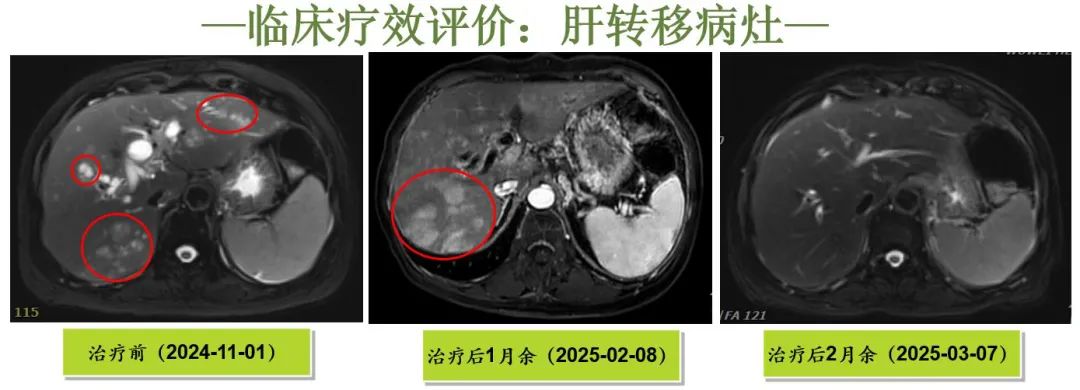

[疗效评价]

CR: